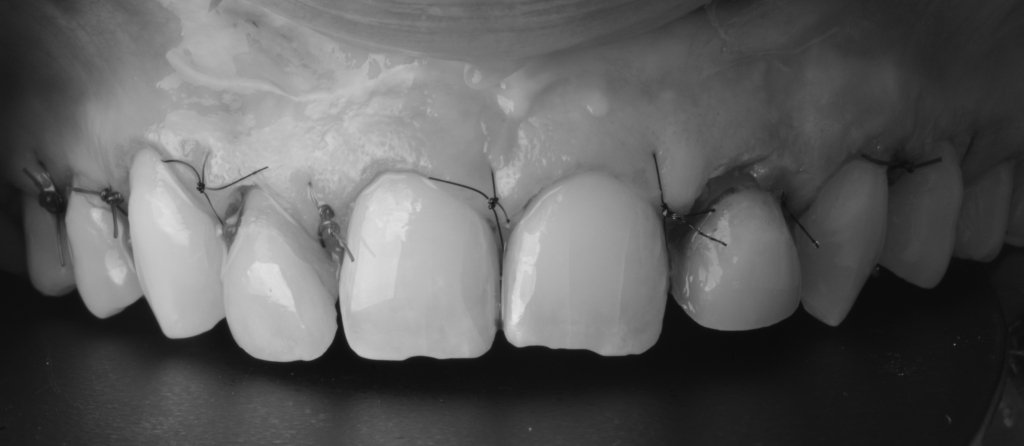

Y vamos de Azul (NIC TONE) sin linea de terminación, sufrimos el doble..no tenemos donde agarrar el Clamp y sobre todo donde realmente termina la carilla…

Voy siempre de 2 en 2, claramente cemento antes las Coronas, que me ayudaran a «clampar» y luego las carillas. Pero normalmente empiezo con los laterales que están en el medio y suelen robar el espacio a los otros

Tomaros vuestro tiempo para limpiar bien bien, no os vais a arrepentir en la vida..

Keep calm trás la retirada del Dique, esta encía volverá a su sitio (si habéis hecho bien la cirugía por supuesto).